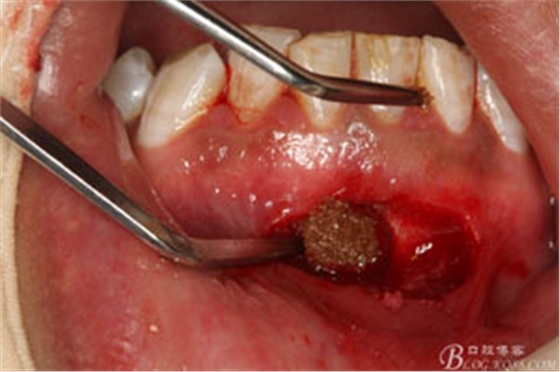

圖16. 缺損骨腔填塞一枚膠質(zhì)銀